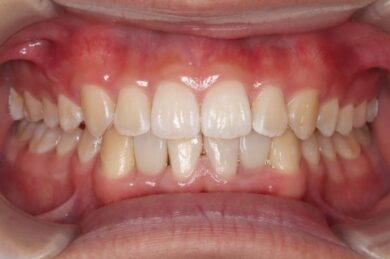

• 治療後

インビザラインの治療計画では、下顎前歯がより美しく審美的に並ぶよう、ご自身の歯とインプラントの歯がほぼ同じ幅径になるよう計算し配列を行いました。

インプラントは世界シェアNo,1の「ストローマン」インプラントを採用。若年者の方も安心して長期的にお使いできるよう配慮しています。